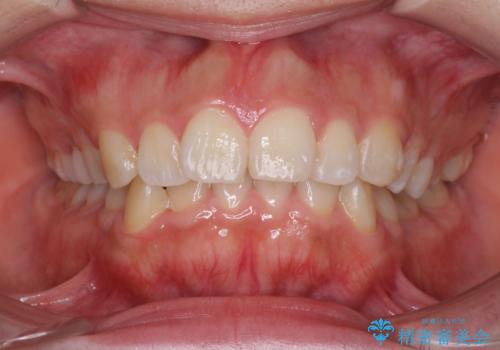

- 歯並びがガタガタなのと、口が閉じずらいのを主訴に来院されました。

口元もすっきりとすることがで、口も自然に閉じるようになりました。